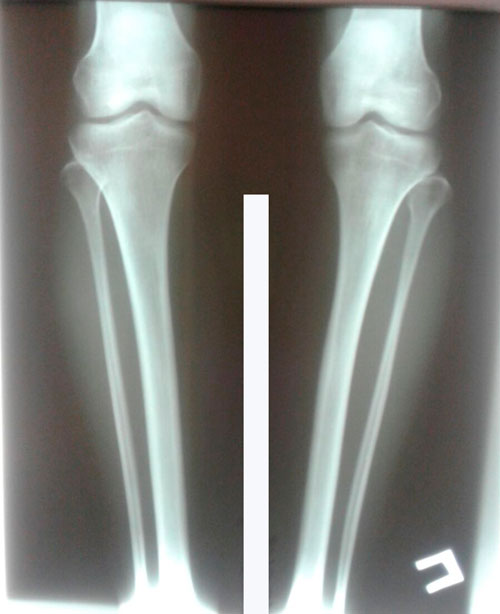

Пациентка - 30 лет. Экибастуз.

Дата операции 16.01.2018г.

рентген до операцции